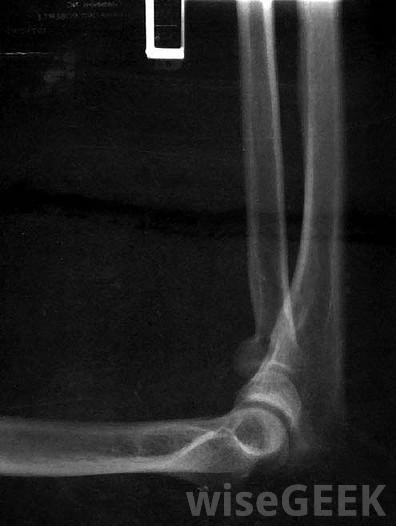

肘關節炎是指由肘關節炎癥引起的一種疾病。通常情況下,這種情況會導致腫脹、疼痛和活動受限。此外,早晨僵硬和無法伸直肘部也可能存在。通常,肘關節炎最常見的原因之一是類風濕性關節炎。通常,損傷和骨關節炎也可引起肘關節炎,但癥狀和表現相似。肘關節炎是肘關節的炎癥一般來說,診斷肘部關節炎要看體格檢查和完整的病史。體格檢查可能會發現肘關節腫脹和壓痛,以及發紅和發熱。除了體格檢查外,一般情況下,在肘關節炎的情況下,x光可以顯示關節變窄、身體松動或骨質疏松。偶爾,當關節炎是由損傷引起時,x光可能表明肘關節骨連接不當肘部x光片可用于診斷肘關節炎。肘關節炎的非手術治療通常包括活動受限,疼痛管理和物理治療。常用的藥物包括消炎藥、對乙酰氨基酚和皮質類固醇有時,建議使用抑制免疫系統的藥物和抗瘧疾藥物。物理療法可以有效地減輕疼痛和恢復活動能力。對受影響的關節進行冷或熱療法,加上治療性鍛煉,通常可以顯著恢復活動范圍物理療法是治療肘關節炎的常用方法。偶爾,當非手術治療無效時,外科手術可能是必要的。一種能有效緩解肘關節炎癥狀的外科手術是滑膜切除術,即切除受影響的滑膜。另一種常見的手術是關節鏡手術,這需要使用小器械通過一系列小切口取出病變碎片。這種微創手術大大縮短了恢復時間,降低了感染的風險。一般來說,肘關節炎的非手術治療可以有效地減少癥狀,但是,因為它可能是一種慢性疾病,關節炎治療可能需要持續進行。在病情發作期間,經常建議減少活動,因為不這樣做可能會導致病情惡化,通過適當的醫療管理和干預,肘關節炎通常可以很好地耐受,有時甚至沒有癥狀由于其他的醫學狀況可以模擬肘部關節炎的癥狀和表現,所以做出明確的診斷是很重要的。當診斷有問題時,可能需要進一步的評估,如血液檢查。某些疾病,如痛風,可以偽裝成肘關節炎,當痛風出現時,血液檢測常顯示尿酸水平升高。尿酸水平升高會導致關節疼痛,包括肘部和腳趾。肘關節。